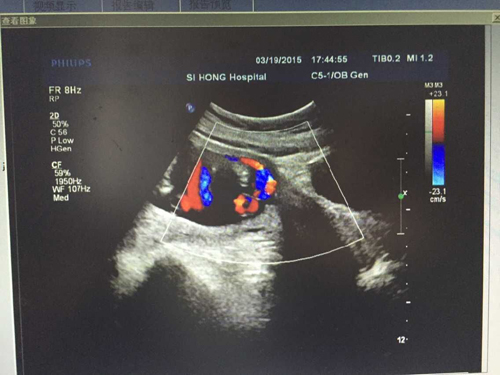

手术中,孕妇被切开子宫下段,发现血管附着于胎膜上面,胎膜上弥漫着怒张的血管,暴露的子宫下段如一颗跳动的心脏。此刻证实了四维彩超室早在孕妇怀孕24周时就已确诊的前置血管。

做四维彩超最佳的时间为怀孕22-28周内,其最佳检查时间怀孕24周,此时胎儿发育基本成形,羊水量适中,较适合做胎儿畸形筛查。另外,四维彩超还能将宝宝在宫腔内的运动情况自动拍摄下来,并且可以录制成光碟,作为最珍贵的留念。